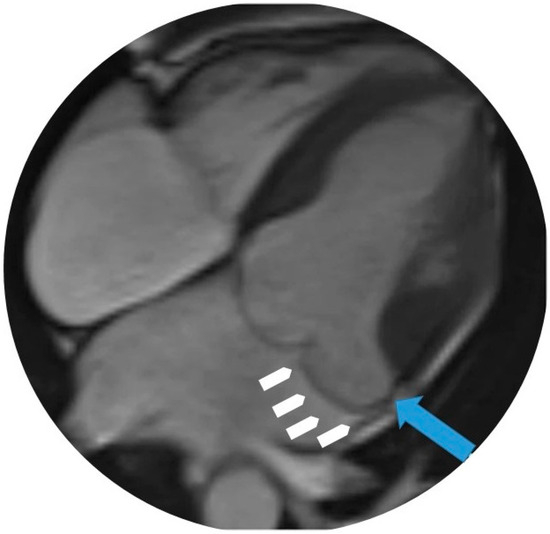

4.4. Cardiovascular Magnetic Resonance (CMR)

- Hussain, N.; Bhagia, G.; Doyle, M.; Rayarao, G.; Williams, R.B.; Biederman, R.W.W. Mitral annular disjunction; how accurate are we? A cardiovascular MRI study defining risk. Int. J. Cardiol. Heart Vasc. 2023, 49, 101298. [Google Scholar] [CrossRef]